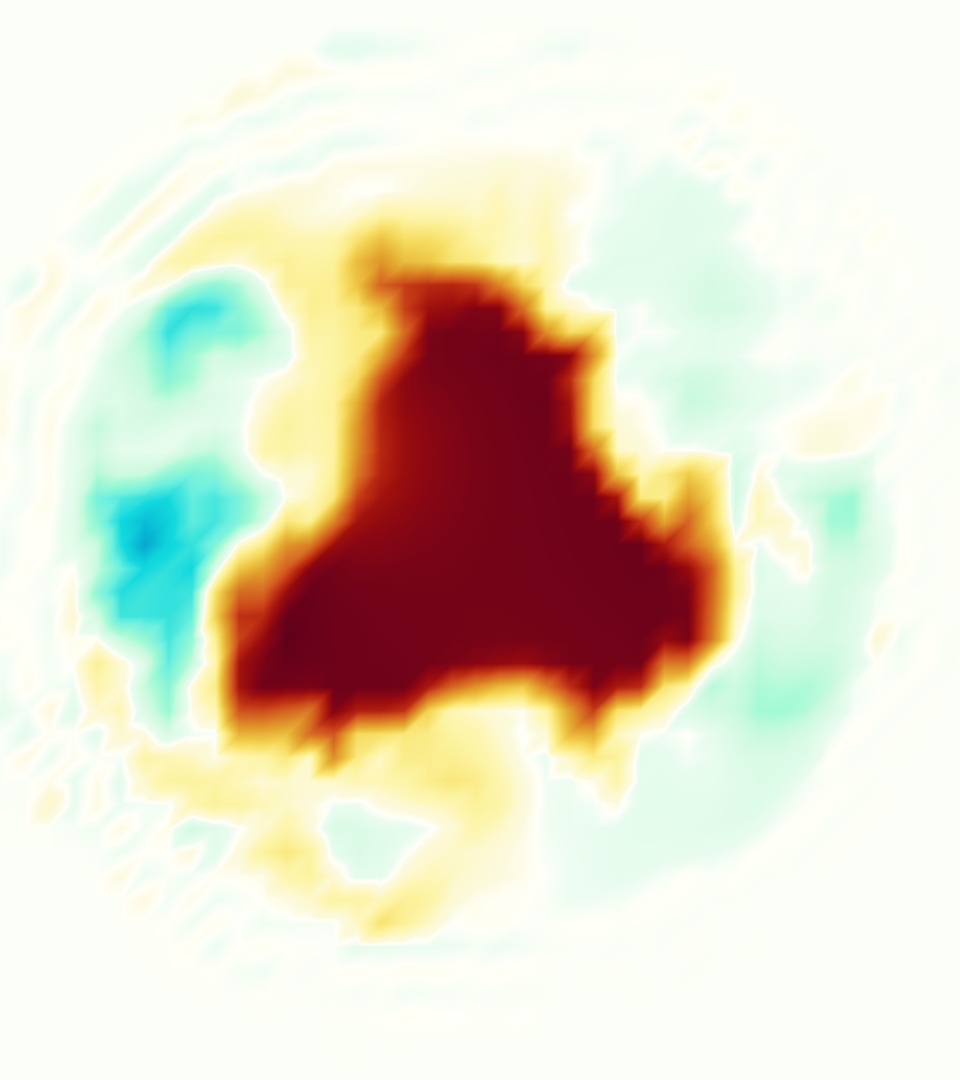

Slice views of the (axial) component of fluid velocity in the axial plane, orthogonal to the flow direction, show that the simulation replicated the development of the jet over the cardiac cycle. At each phase, the simulation matched the forward speed of the core of the jet and the locations of reverse flow back towards the valve annulus. While there are some differences in the shape of the jet at certain phases and locations, the simulation clearly produced the general dynamics of the cardiac cycle that are seen in the experiment.

At = 0, the axial slice directly at the valve annulus shown in columns 1 and 2 in Figure 6, there was excellent agreement between the simulation and experiment over the cardiac cycle in the speed and shape of the jet through the valve. In both cases, the axial velocity increased as the flow accelerated during systole and the valve leaflets opened, then decreased during diastole with slight negative velocity before the valve leaflets were fully closed. The forward flow through the valve annulus did not form a full circle, but rather developed a triangular shape with a point of the triangle forming along the interior curve of the vessel, at the bottom of the axial slices. At = 0, the points of this triangular jet shape aligned with the commissures of the valve. This shape persisted during peak systole and was well-matched by the simulation.

The axial slice = 0.625 cm, shown in columns 3 and 4 in Figure 6, cut through the support scaffolding of the valve and the leaflets when they are open. In the experimental data, the shape of the jet changed as it moved downstream. A triangular shape occurred, but the points were then aligned with the middle of each open leaflet as opposed to the commissures. Those points were also more rounded than they were at = 0. The peak velocity of the jet was faster at = 0.625 cm than at = 0, as the flow accelerated through the open valve leaflets. The simulation produced these features at = 0.625 cm. The triangular shape of the jet shifted similarly, and its speed increased compared to the upstream slice. As the flow decelerated into diastole, the jet shape remained roughly triangular but diminished in intensity before disappearing after valve closure.

The jet continued to develop at = 1.25 cm, an axial slice immediately downstream of the valve scaffolding and open leaflets, shown in columns 5 and 6 in Figure 6. In the experimental data, the points of the triangular jet shape extended further towards the vessel wall. In addition, regions of reversed flow developed in the locations downstream of the commissures, resulting in curved sides to the shape of the jet. Each tip of the jet was unique, due to variations in the individual leaflets in the physical bioprosthetic valve. These variations are apparent in the velocity fields, possibly because the jet edges are similar enough cycle to cycle that irregularities are still being captured even with phase averaging. Further discussion of these features can be found in Schiavone et al. [39], which showed that the jet tip shapes occurred in different pulmonary anatomies, demonstrating that they were likely due to inherent properties of each leaflet. The leaflets in the mathematical model of the valve are identical, so these nuances in leaflet variation could not be replicated. The simulation did capture some of the extension of the tips of the jet, as they were closer to vessel wall at slice = 1.25 cm than = 0.625 cm. The curves in the triangular sides of the jet were also present in the simulation, though they were less pronounced than the experimental data. At both = 0.625 cm and = 1.25 cm, the jet shape in the simulation was smoother than the jet in experiment. It is possible that the free edges of the leaflets in the mathematical model are not fully replicating the behavior of the physical leaflets of the bioprosthetic valve, in particular the amplitude or frequency of leaflet flutter, leading to the variations seen in the jet shape at = 1.25 cm downstream of the leaflet edges. The simulation, however, does capture the key features of the triangular shape and speed of the jet. Overall, qualitative comparisons demonstrated that the simulation reproduced key features of the flow during systole and diastole.